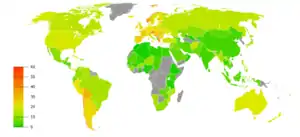

Usage

Though tobacco may be consumed by either smoking or other smokeless methods such as chewing, the World Health Organization (WHO) only collects data on smoked tobacco.[1] Smoking has therefore been studied more extensively than any other form of tobacco consumption.[2]

In 2000, smoking was practiced by 1.22 billion people, predicted to rise to 1.45 billion people in 2010 and 1.5 to 1.9 billion by 2025. If prevalence had decreased by 2% a year since 2000 this figure would have been 1.3 billion in 2010 and 2025.[290] Despite dropping by 0.4 percent from 2009 to 2010, the United States still reports an average of 17.9 percent usage.[61]

The WHO states that "Much of the disease burden and premature mortality attributable to tobacco use disproportionately affect the poor". Of the 1.22 billion smokers, 1 billion live in developing or transitional nations. Rates of smoking have leveled off or declined in the developed world.[294] In the developing world, however, smoking rates were rising by 3.4% per year as of 2002.[291]

The WHO in 2004 projected 58.8 million deaths to occur globally,[295]: 8 from which 5.4 million are smoking-attributed,[295]: 23 and 4.9 million as of 2007.[296] As of 2002, 70% of the deaths are in developing countries.[296]